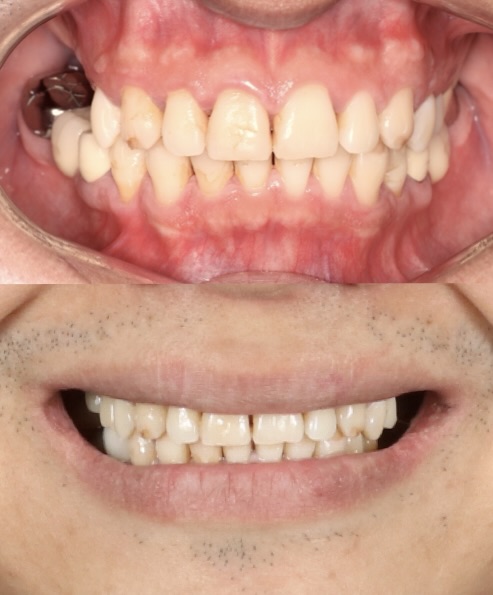

Before

After

ALL-ON-4

This patient transitioned from a removable denture to a fixed full-arch prosthesis using the All-on-4 technique. With strategically placed implants and immediate loading, a new confident smile was delivered within a single day. Work done by our expert team at Moral Dental Clinic